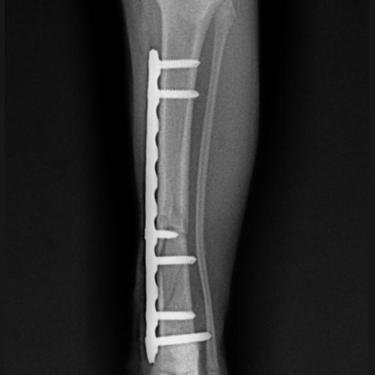

Fijación interna: precisión y estabilidad

La fijación interna es ideal cuando se busca una reducción anatómica y una estabilidad rígida.

Incluye:

Placas y tornillos

Placas bloqueadas (LCP)

Indicaciones:

Fracturas diafisarias y metafisarias

Casos que requieren alta precisión

Pacientes con buen estado de tejidos blandos

Ventajas:

Excelente control de alineación

Mayor estabilidad mecánica

Permite recuperación funcional temprana